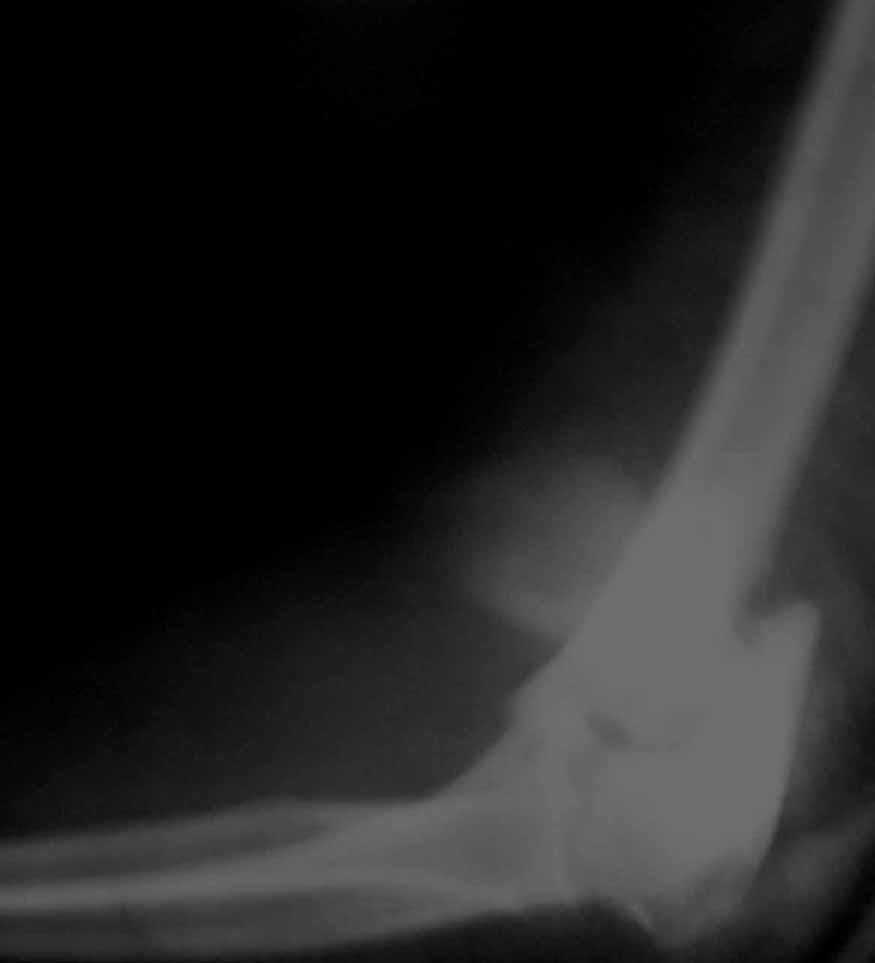

Примерный случай, только перелом был открытый, в задне-медиальной стороне рана около 2 см по характеру "изнутри кнаружи", неврологический статус со слабостью сгибания мизинца, также слабая абдукция и аддукция указательного пальца и сгибания в кисти.

Больному сделали обработку и наложили временный аппарат внешной фиксации плечо-предплечье.

На шестой день сделали открытую репозицию чрезлоктевым доступом двумя locking plate, локтевой нерв был ушибленным, после операции положительная динамика в Flexor Carpi Ulnaris. Фиксацию локтевого отростка произвели tension band technique с дополнительным шурупом.

Этапы операции на снимках....